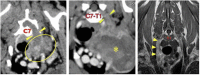

This case report describes the diagnosis, management and outcome of three dogs with peripheral nerve sheath tumors (PNSTs) involving the brachial plexus, C7 (case 1), C8 (case 2), and C8 and T1 (case 3) spinal nerves and nerve roots with intrathoracic invasion. Surgical resection required thoracic limb amputation and removal of the first rib, facilitating a novel lateral approach to the spinal nerves and foramina in all cases. This was followed by hemilaminectomy and rhizotomy in cases 1 and 2. Adjunctive radiotherapy was then performed in all dogs. All three dogs regained a good quality of life in the short-term following surgery. Two were euthanased after 3 and 10 months, following detection of a pulmonary mass in one case and multiple thoracic and abdominal masses in the other. The third dog was alive and well at the time of writing (7 months post-surgery). This surgical approach facilitated good access and allowed gross neoplastic tissue to be resected. The ease of surgical access was dependent, to a degree, on the size of the patient. This surgical approach can be considered in cases of PNSTs involving the caudal cervical or cranial thoracic spinal nerves and nerve roots. Adjunctive radiotherapy should be considered as part of a multi-modal approach to these challenging tumors due to the difficulty of achieving clean margins, particularly proximally, even with optimal surgical access.